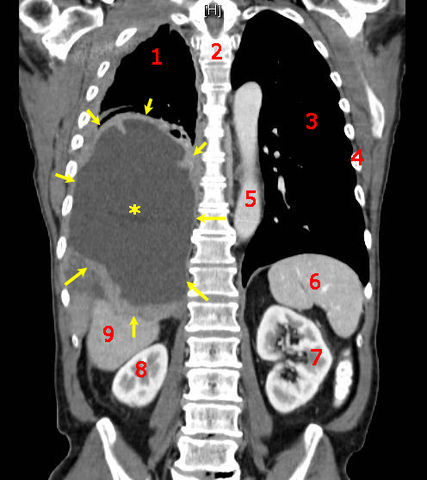

Malignant Mesothelioma, coronal CT scan.

Legend: the malignant mesothelioma is indicated by yellow arrows, the central pleural effusion is marked with a yellow star. (1) right lung, (2) spine, (3) left lung, (4) ribs, (5) aorta, (6) spleen, (7) left kidney, (8) right kidney, (9) liver. |